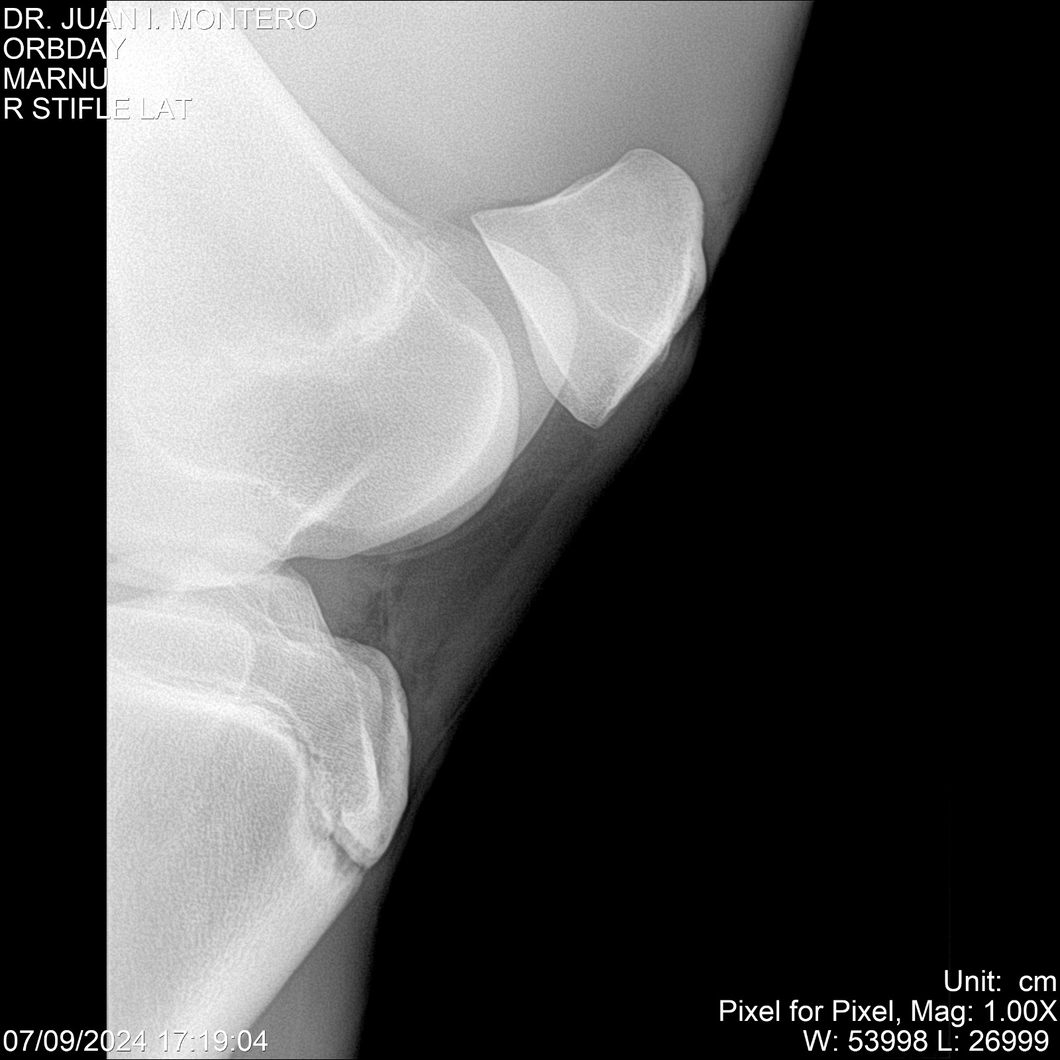

• Empresa: Abelenda N. R., Walter Hugo